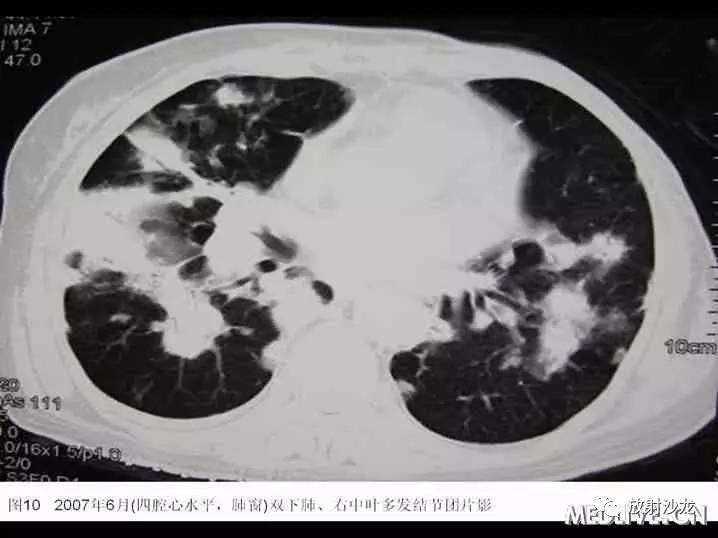

入院后患者最高体温在38℃左右,给予“拜复乐及大扶康”治疗后无显效,复查胸部CT提示肺内病变较2007年3月有加重(见图9-12),遂再次行CT引导下经皮肺穿。穿刺后患者最高体温维持在39℃左右,考虑感染不能完全除外,于2007年6月19日起加用稳可信0.5g Q8h及复达欣1.0g Q8h,6月21日加用口服大扶康200mg Qd,发热未见改善。结合两次肺穿及外院VATS的标本,病理科诊断“肺Castleman病(多中心型)(见图13)” 免疫组化:CD3(+)、CD20(+),AE1/AE3(+),CD21(+)”。6月21日转入血液科化疗,并于6月22日予CHOP方案化疗(CTX 600mg d1, 400mg d4, 西艾克4mg d1, 艾达生80mg d4, 强的松80mg d1-5)。化疗后未再发热,咳嗽、咳痰症状缓解,6月27日复查CXR示右下肺团块影较1月前吸收予以一疗程CHOP化疗后,患者体温正常,复查胸片提示右下肺阴影较前有明显吸收。后又间断予以CHOP方案化疗3程,2008年2月初,因受凉后发热,出现渐加重的气短,家属及患者放弃进一步诊疗,于2008年2月下旬去世。